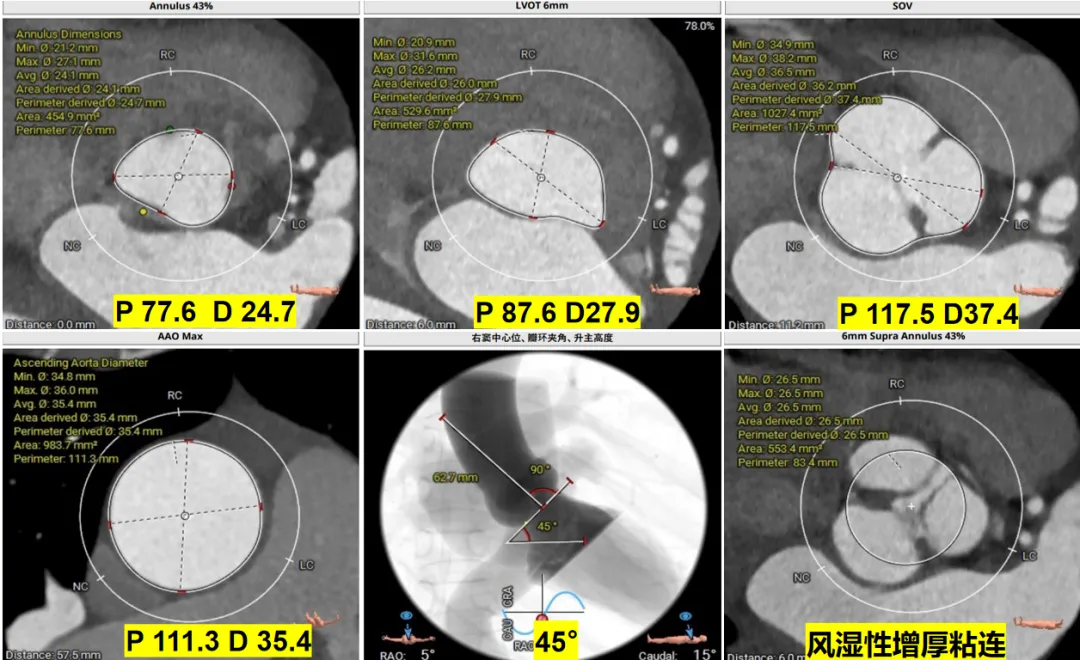

Case 3

瓣上风湿性粘连伴有狭窄重度反流

01

术前CT评估

02

瓣膜选择

根据瓣环与 LVOT-6 mm 平面,备后扩解决瓣上,避免瓣周漏,选择:M 号 TaurusTrio